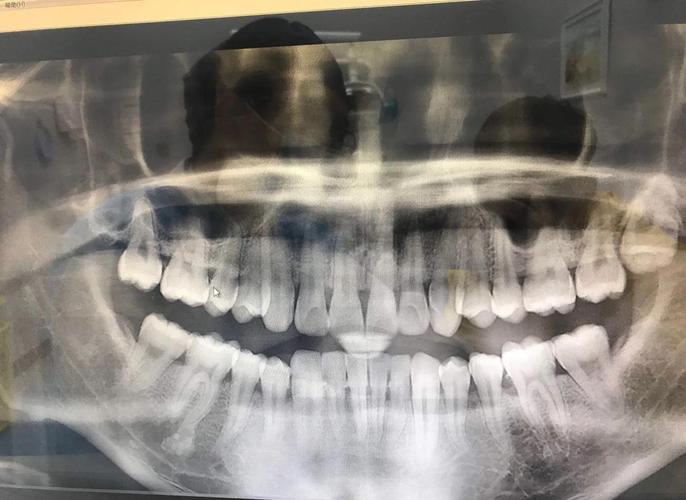

(图片来源网络,侵删)- 牙齿长度、宽度、倾斜度测量不准: 这是最直接的影响,正畸治疗极度依赖精确的牙齿和颌骨尺寸测量(如牙冠宽度、牙根长度、牙齿倾斜角度),角度偏差会导致这些测量值出现显著误差,直接影响医生对牙齿拥挤程度、咬合关系、骨量需求等的判断。

- 颌骨关系判断错误: 在头颅侧位片中,上下颌骨的前后、垂直关系(如ANB角、颌平面角等)是诊断骨性错颌畸形的关键指标,角度过大(尤其是侧位片时头部旋转或仰俯角度不对)会严重扭曲这些角度,导致对骨骼问题的误判(比如把骨性错判成牙性错,或反之)。

- 漏诊或误诊: 基于失真的影像,医生可能无法准确识别某些问题,例如埋伏牙的位置、阻生牙的方向、骨量不足的程度、牙根吸收情况、牙根位置异常(如靠近下颌管)等。